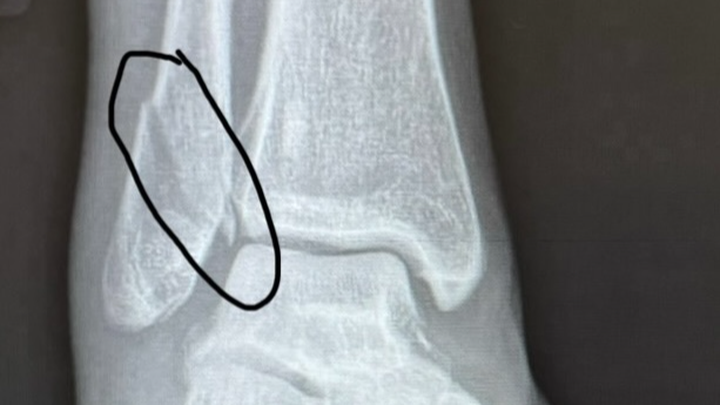

New findings-SEVEN ligaments in my ankle are torn. The bone will need re-broken, repaired and replaced. All ligaments

will need repaired. A scope will need done. 3 incisions.